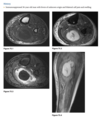

Q

39 yo man fall

Axial T2 fat sat MR - bone contusions in medial patella and lateral femoral condyles (Arrows) with associated tear of medial retinaculum (Arrowhead)

Diagnosis: Acute patellar dislocation relocation

Occurs with internal rotation of femur on fixed and externally rotated femoral condyle - bone contusions on both.

Due to direct impaction, associated with ACL tears.

Radiographs = Lipohaemarthrosis or chip fracture adjacent to donor site of medial facet of patella.

MR findings = Disruption or sprain of the medial retinaculum, lateral patellar tilt or subluxation, lateral femoral condylar and medial patellar osseous contusions. Osteochondral injury to medial patella or lateral femur.